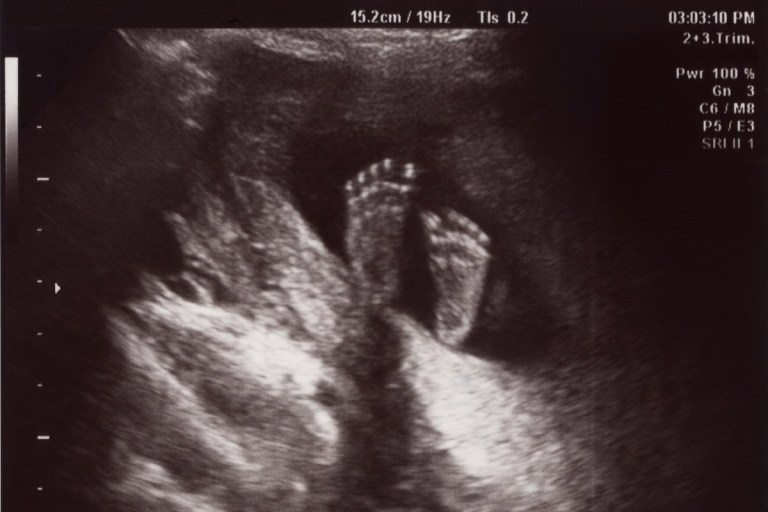

Le-am studiat și respins. Avem toate argumentele și dovezile de partea noastră. Știm de mai bine de un secol că produsul de concepție este uman prin natura sa, viu, se dezvoltă singur. Știm că nu este o parte din mama sa, ci o viață independentă, care se bazează pe mama sa pentru adăpost și hrană. Știm că nu este un parazit, ca o tenie. Știm că nu este un invadator, spre deosebire de ce a spus Judith Jarvis Thomson în absurda ei parabolă cu violonistul și rinichiul. Știm că „viabilitatea” este o trăsătură nu a fătului ci a accidentelor tehnologice și a stării sistemului medical.